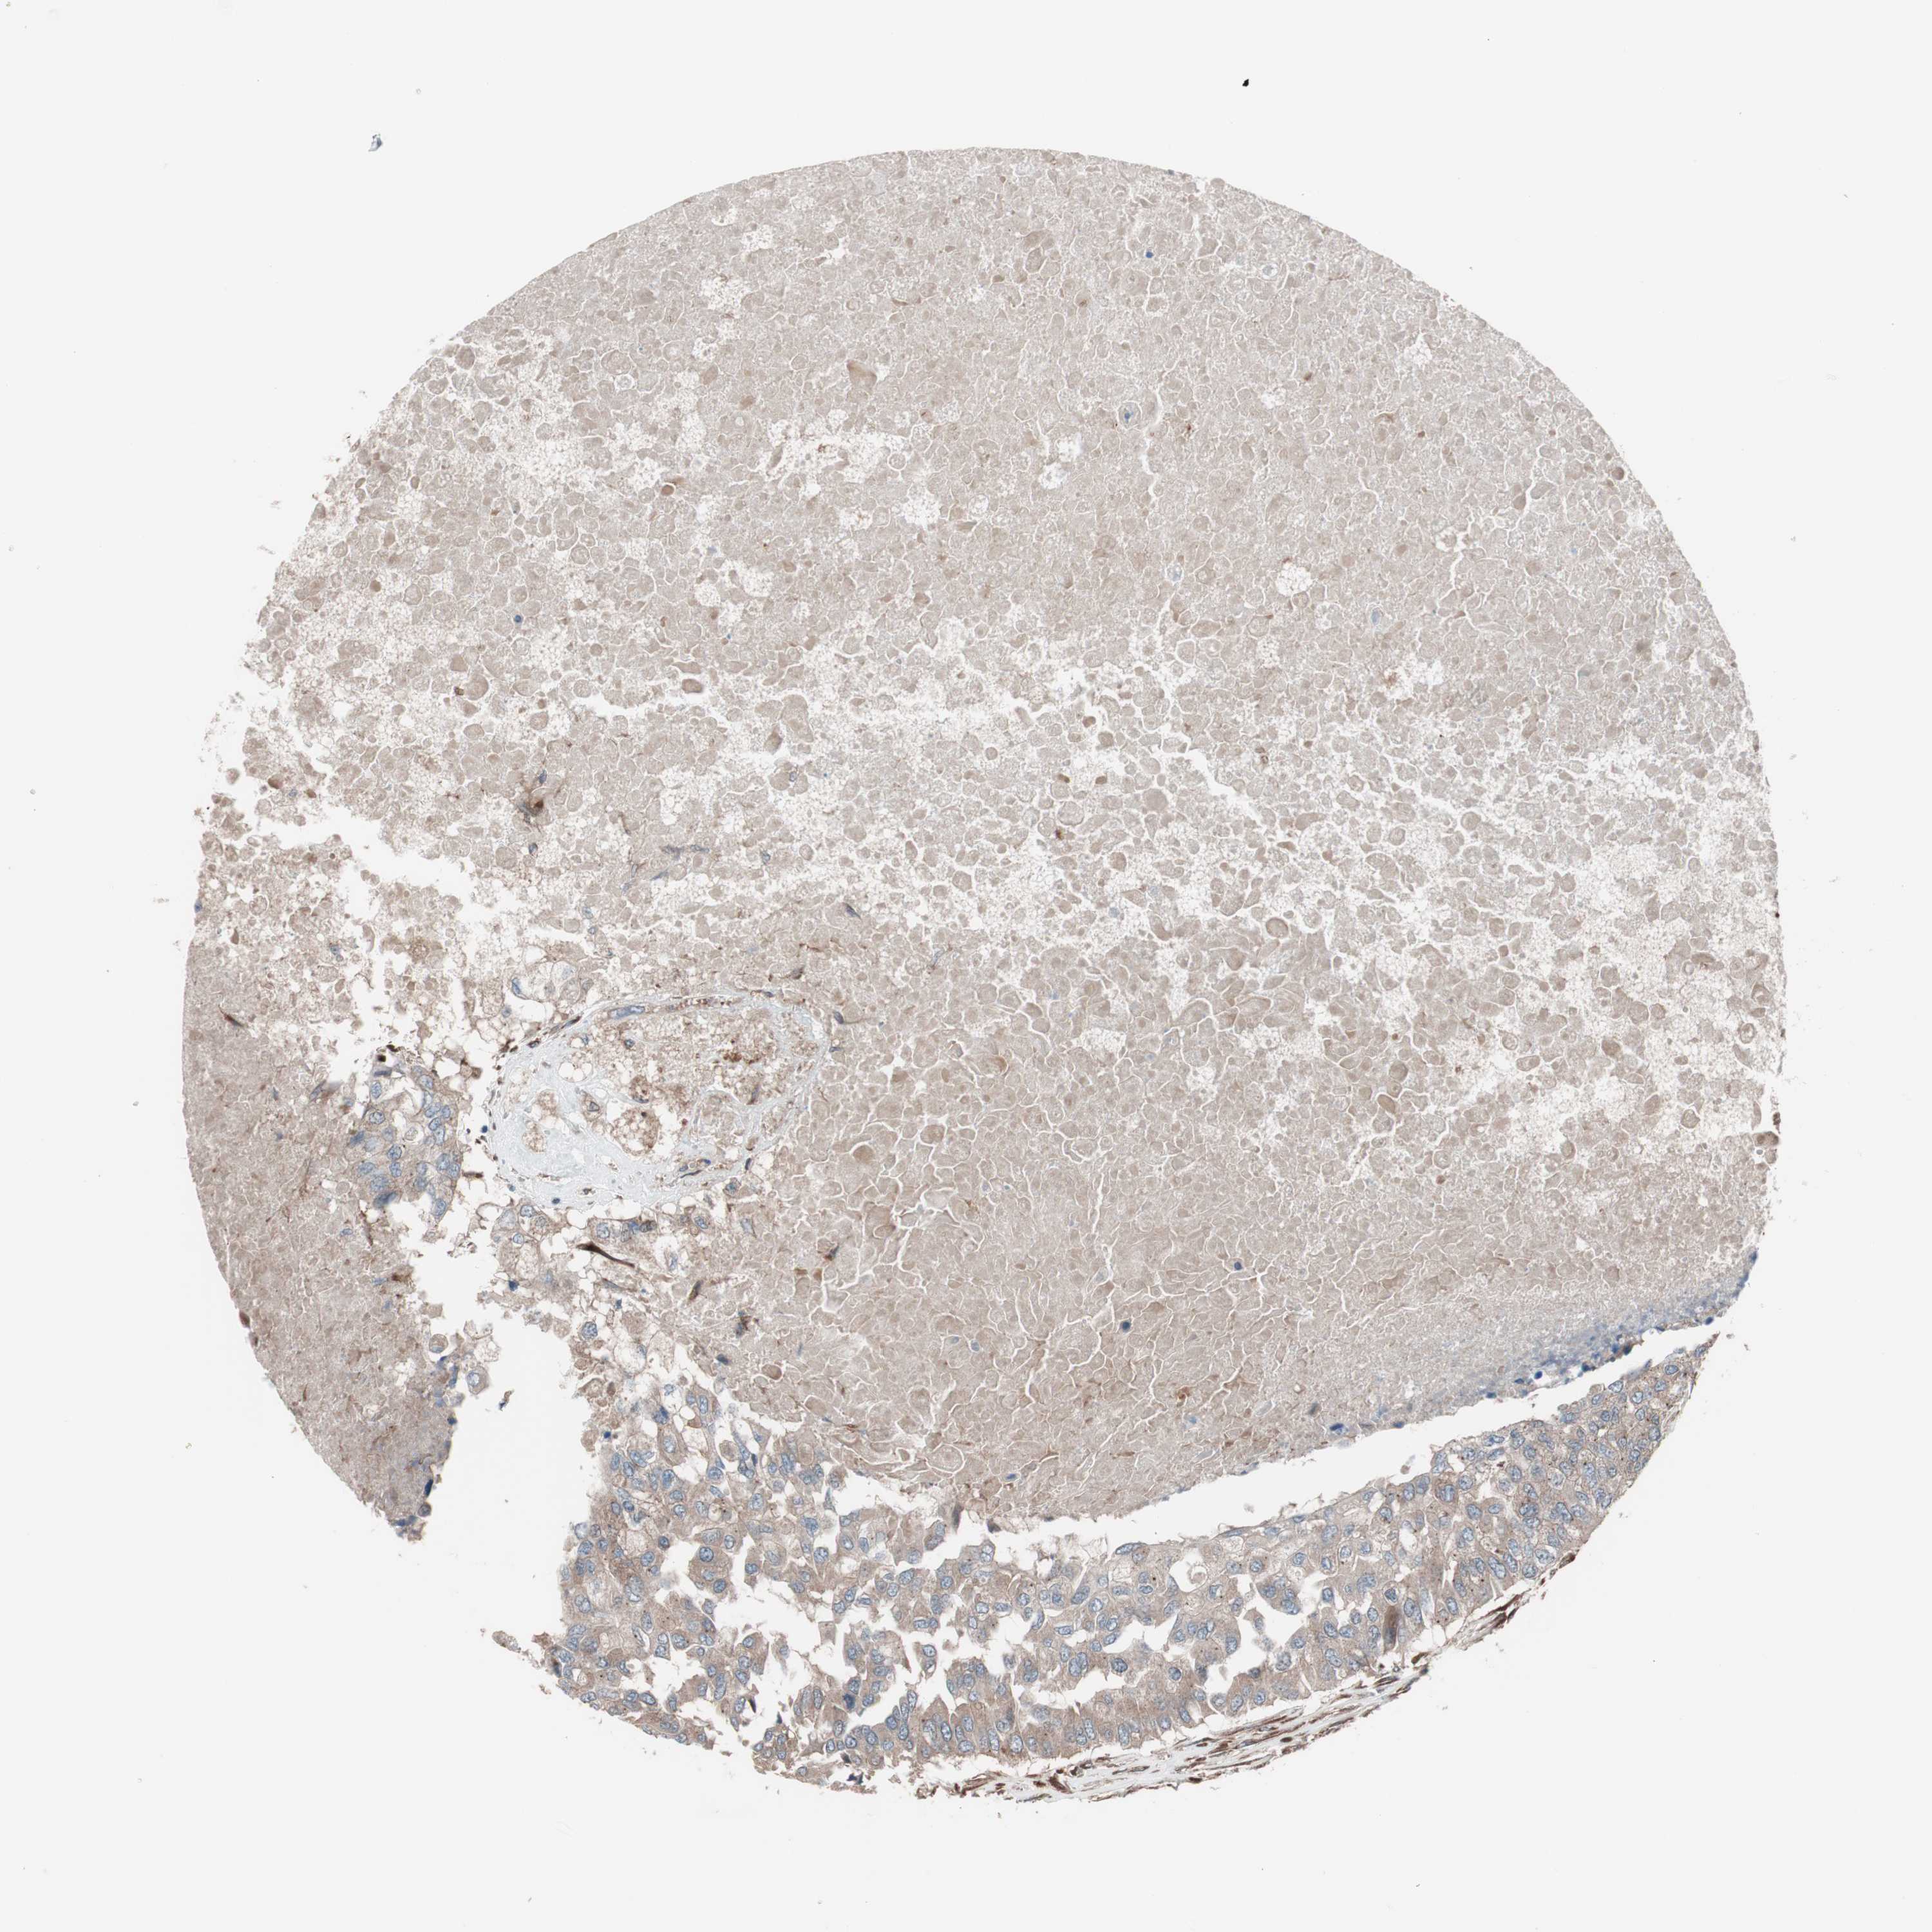

CANCER BREAST CANCER Show tissue menu

BRCA TCGA BRCA VALIDATION PROTEIN EXPRESSION

Breast cancer

Human cancer

Breast invasive carcinoma